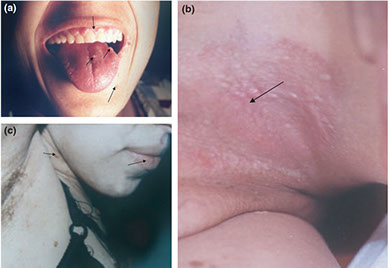

Cowden syndorme. a) Multiple oral fibromas, perioral tricholemmomas; b) papules in the pits; c) perioral tricholemmomas, oral fibromas on lower lip, verrucous papules on neck and chest and skin fibromas